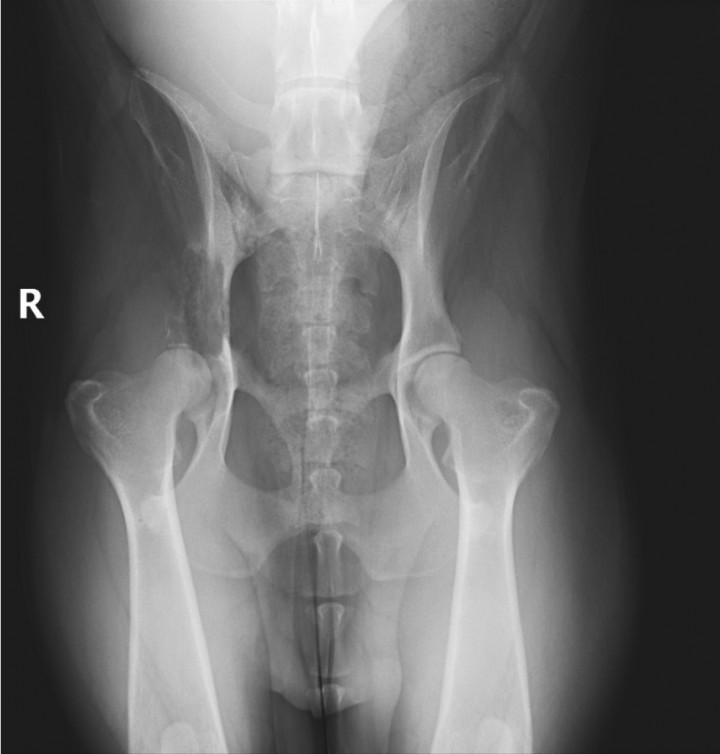

El paciente fue sometido a tratamiento quirúrgico que consistió en una hemipelvectomía craneal externa derecha y amputación de la extremidad posterior derecha, según la clasificación descrita por Bray (2014).[ Bray JP. Hemipelvectomy: modified surgical technique and clinical experiences from a retrospective study. Vet Surg. 2014; 43(1):19-26. [PubMed] ] Se realizó una incisión curvilínea desde la cresta ilíaca hasta un punto caudal al trocánter mayor del fémur. La incisión se extendió medialmente desde el pliegue inguinal hasta el isquion. Según Bray (2014), la técnica descrita para realizar una hemipelvectomía craneal externa consiste en la extirpación de la extremidad pélvica ipsilateral, el acetábulo y el ilion, extendiéndose hasta el nivel de la sínfisis púbica. Sin embargo, en este caso no se extendió hasta la sínfisis púbica, sino que se realizó una osteotomía en la región del pecten del pubis mediante el uso de una sierra oscilante. La osteotomía del isquion fue realizada con sierra oscilante y la articulación sacroilíaca fue desarticulada mediante el uso de martillo y osteotomo. Esta técnica permite preservar el lugar de origen de los músculos semimembranoso/semitendinoso, que pueden utilizarse para el cierre del defecto, los cuales fueron utilizados de esta forma en este caso. Posteriormente, se colocó un drenaje Jackson-Pratt y se procedió al cierre primario del defecto quirúrgico. Se realizó una radiografía ventrolateral de pelvis con propósito puramente académico. (Figs. 3 y 4).

Radiografía postoperatorias de pelvis. (A) Ventrodorsal. (B) Mediolateral. Se observa la hemipelvectomía craneal externa derecha y amputación de la extremidad posterior derecha.